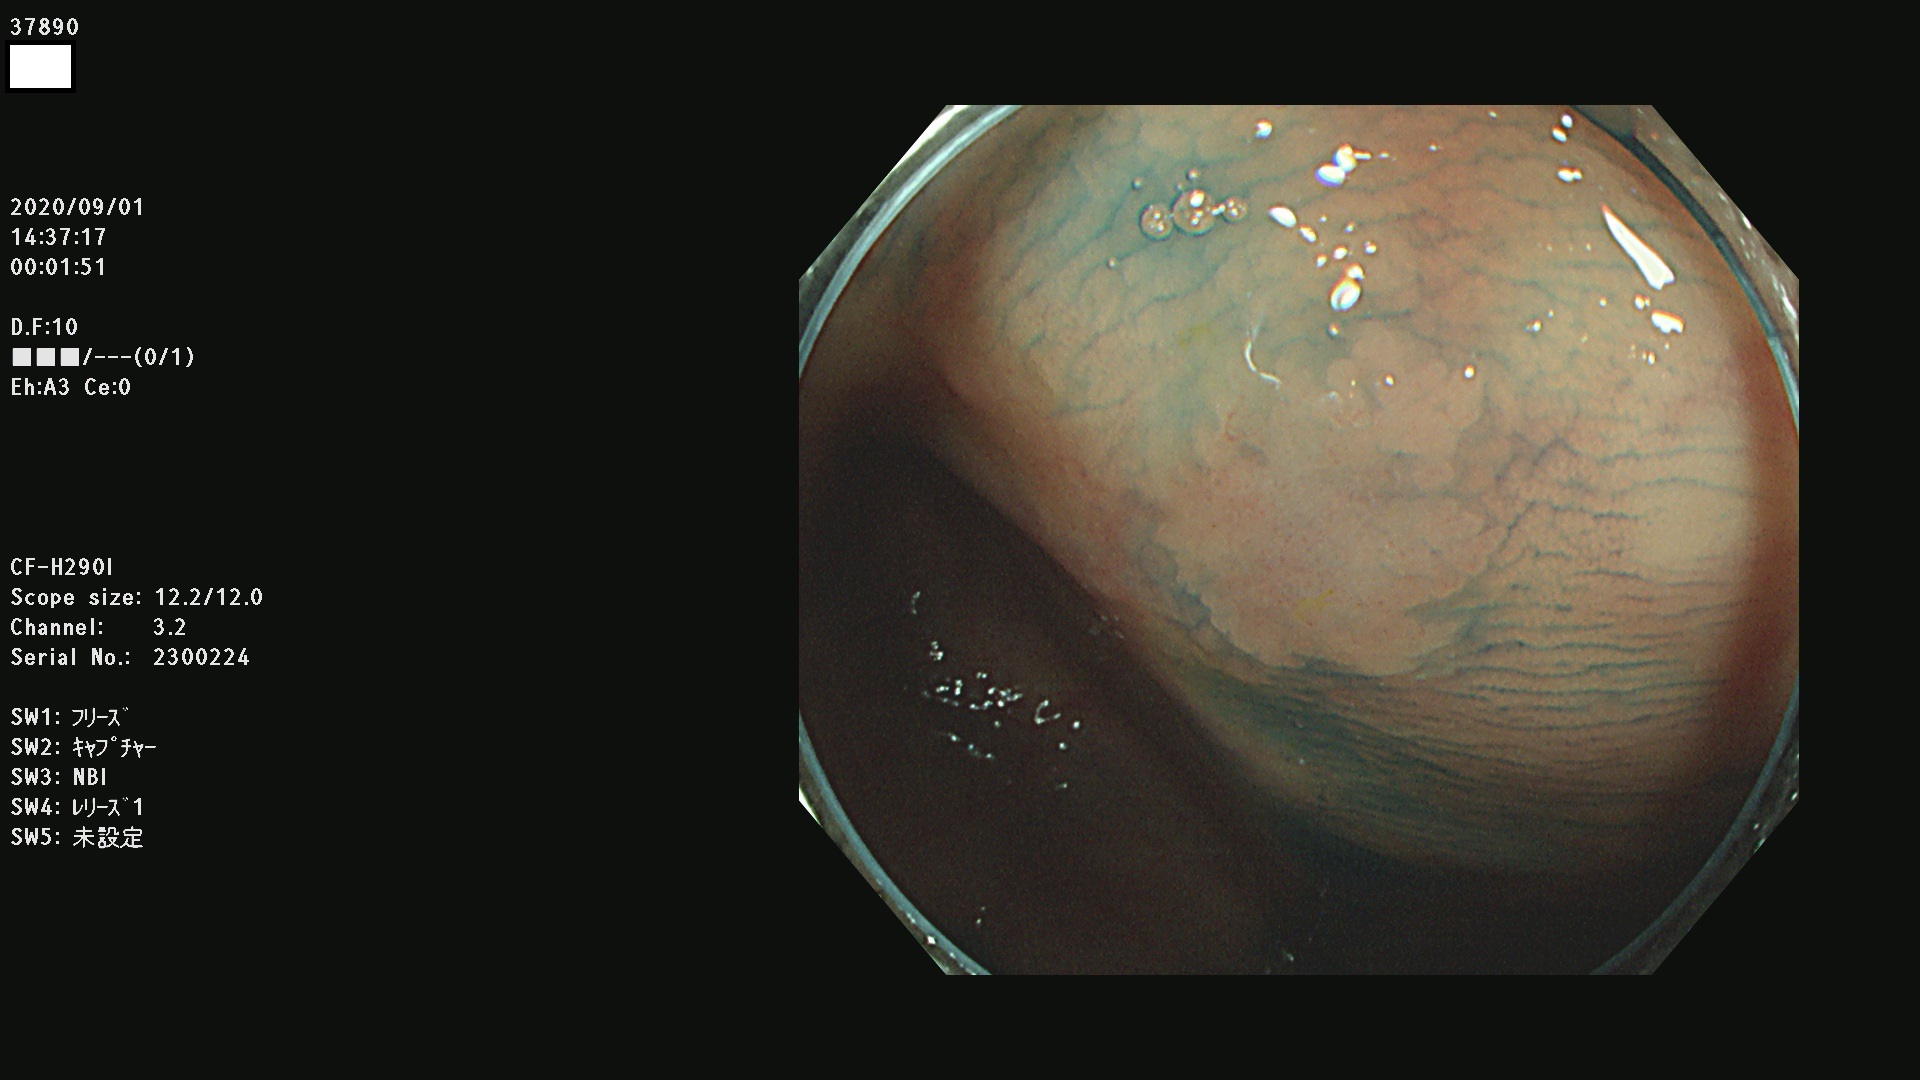

腺腫発見率 75 % (カルテ番号 37800〜37899の100名の方の検査結果で集計)大腸癌検診最新情報

以下のカルテ番号の方に腺腫(Adenoma,Group3〜5)が見つかりました(集計法)

37800(SSAPのみ) 37801 37802 37803 37804 37805 37806 37807 37808 37809(SSAPのみ) 37810 37811 37812 37813 37814 37815 37817 37818 37819 37820 37821 37822 37824 37825 37826 37827 37828 37829 37832 37833 37836 37837(SSAPのみ) 37839 37840 37842 37844 37845(SSAPのみ) 37847 37849 37850 37851 37852 37853(SSAPのみ) 37855 37856 37857 37860 37861 37862 37863 37864 37867 37868 37871 37874 37876 37877 37879 37880 37881 37882 37883 37886 37887 37888 37889 37890 37891 37892 37893 37894 37896 37897 37898 37899

発見困難で危険性の高い平坦型病変(上記100名より抽出) ![]()